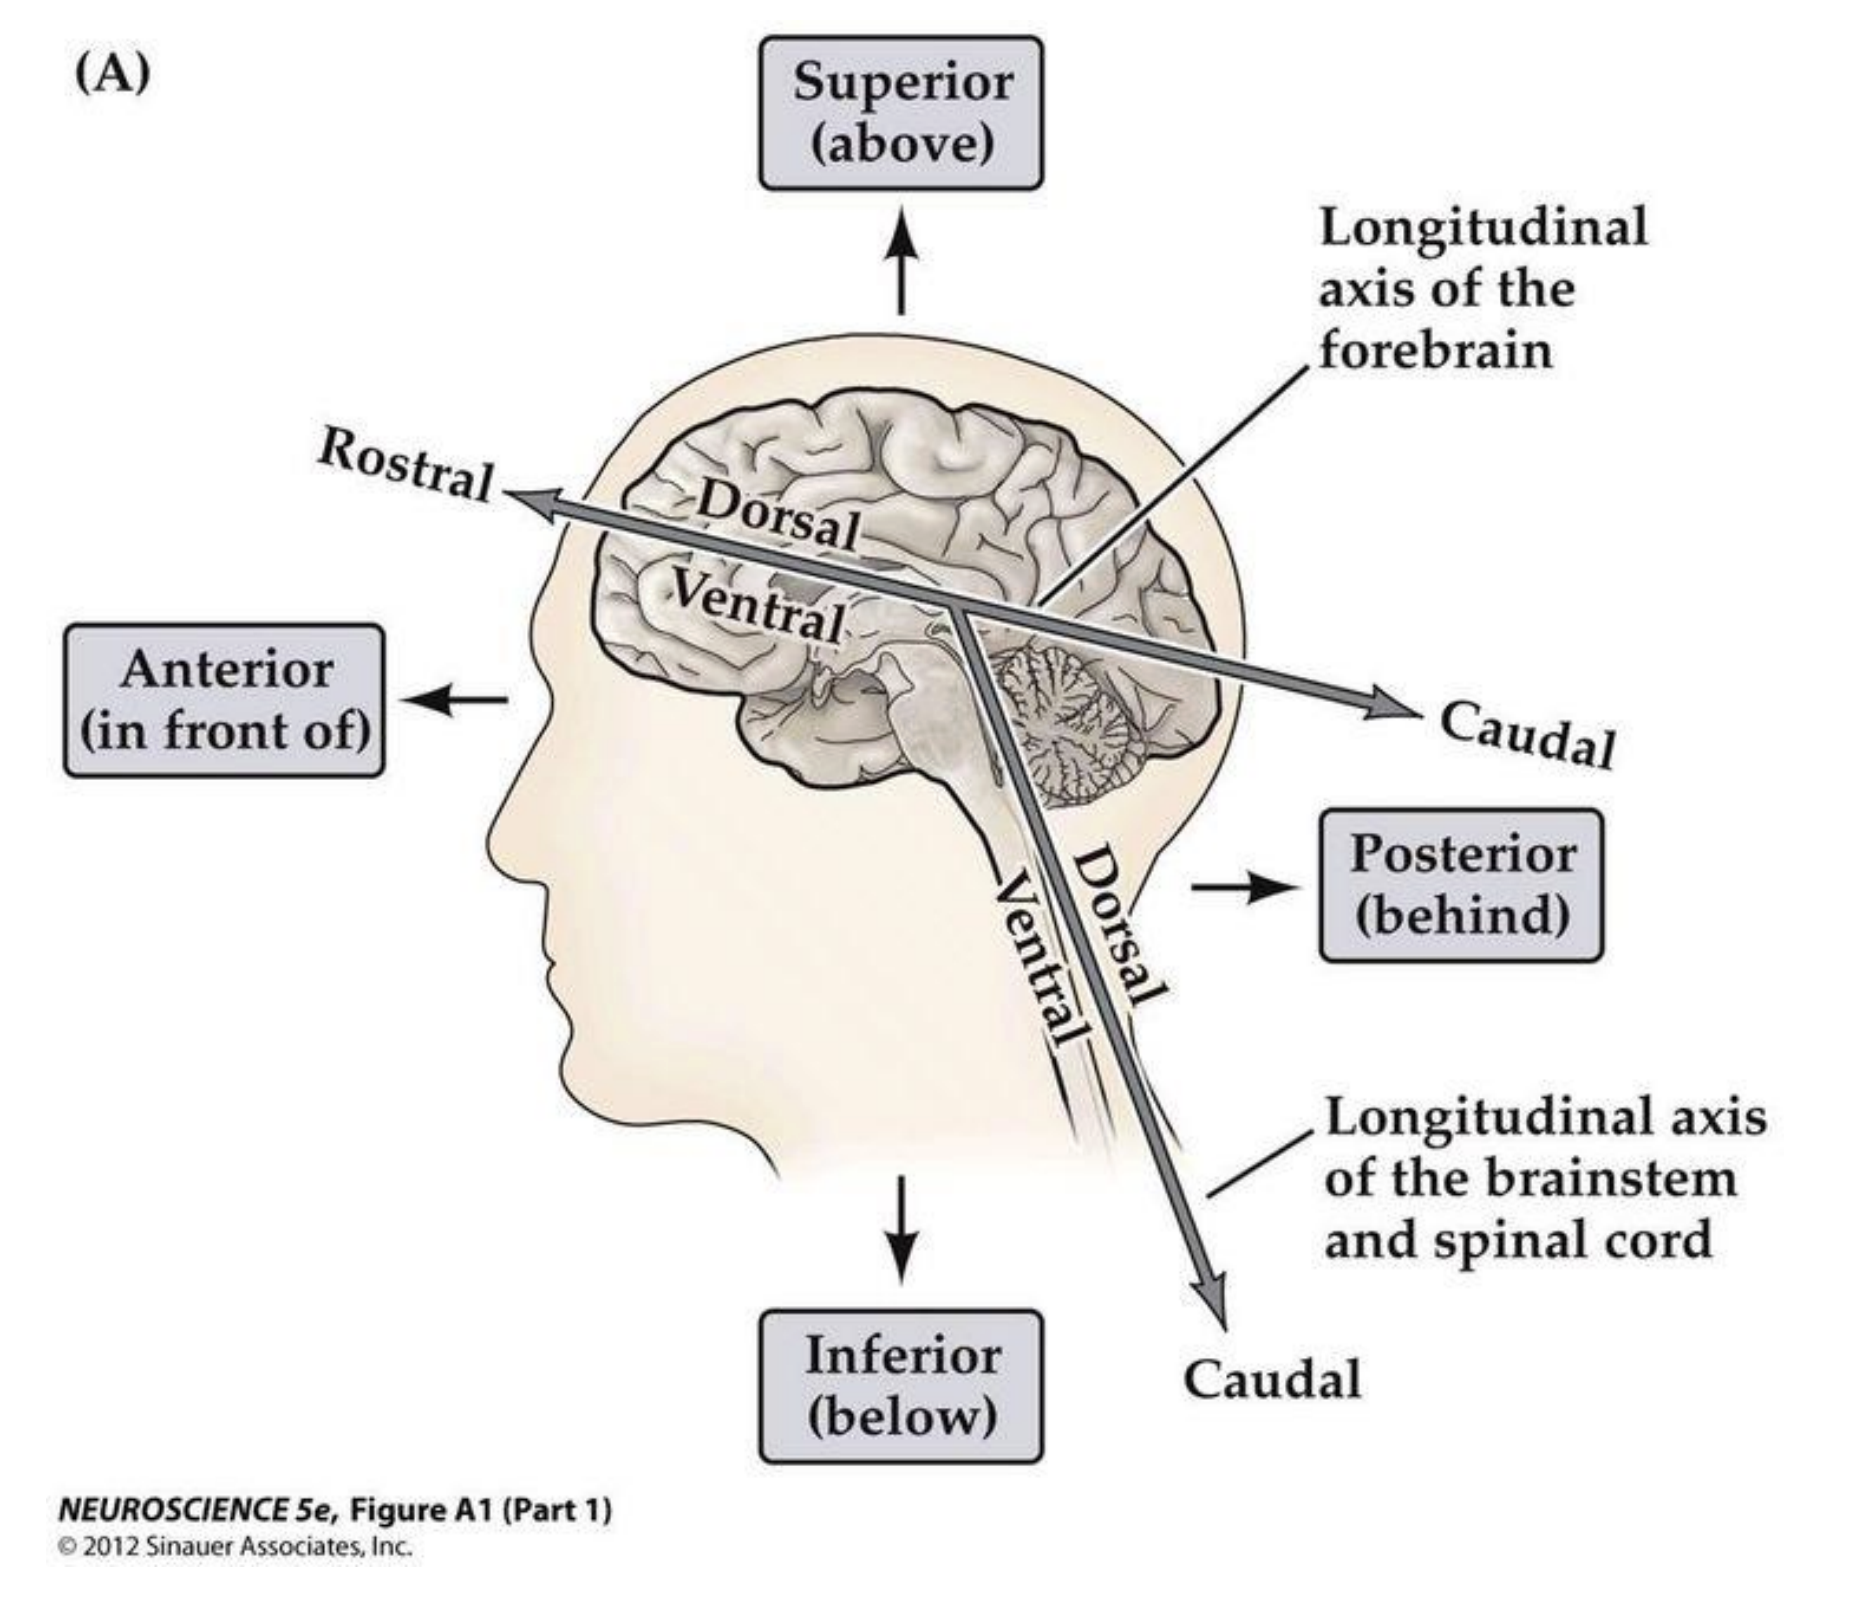

Orientations of brain